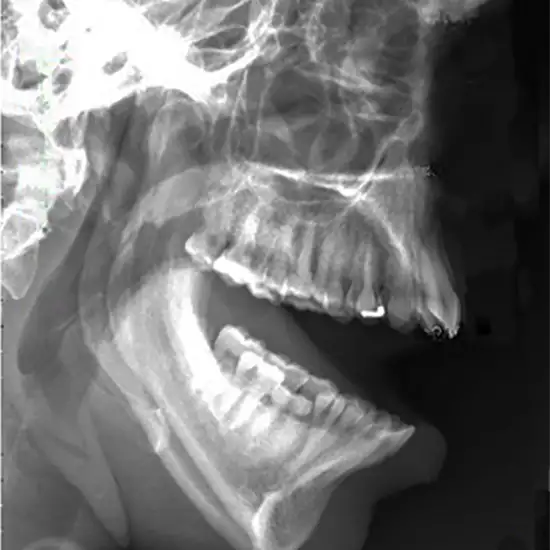

x-ray tm joint open mouth

X-Ray TM Joint-Open Mouth helps doctors figure out if your jaw is out of place or hurt at the TMJ site or in its muscles. If you have pain in your ear, face, jaw, or mouth, or if you have trouble chewing, this test is done.